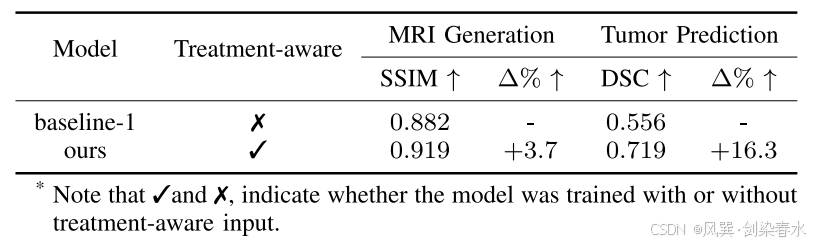

Table 4 | 治疗感知条件化方法的影响:(消融实验)